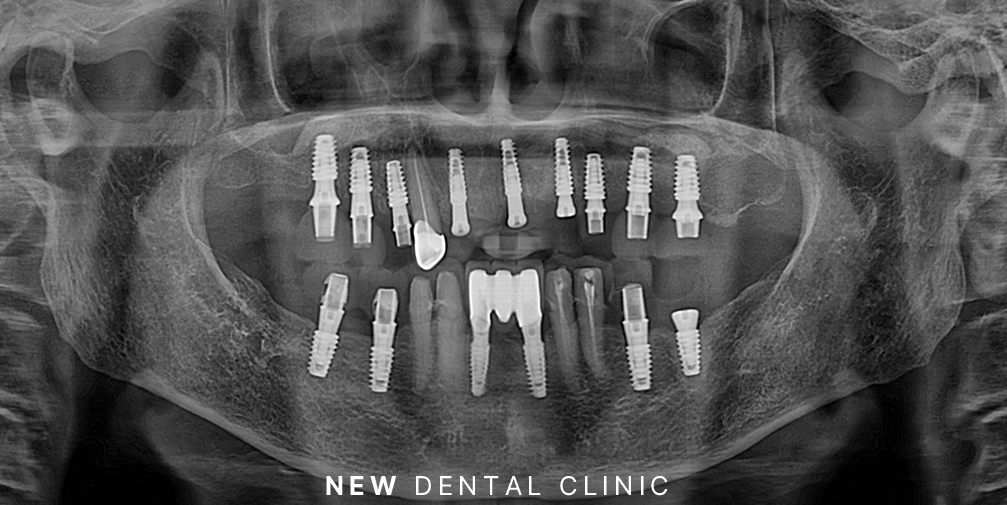

이어서 순차적으로 임플란트 식립과 보철의 과정을 마무리하였습니다.

인공치근을 잇몸뼈에 식립한 후 기존의 잇몸뼈와 단단히 융합될 수 있는 기간을 충분히 기다려준 뒤 수치가 충분한 부위부터 차례로 마무리를 진행하였습니다.

환자분께서는 보험 임플란트 적용 대상자 셔서 앞니 두 개는 보험 임플란트로 진행하셨으며 위쪽의 뼈가 약한 부분은 2차 수술의 과정까지 거친 뒤 튼튼하게 사용하실 수 있도록 마무리를 하였습니다.